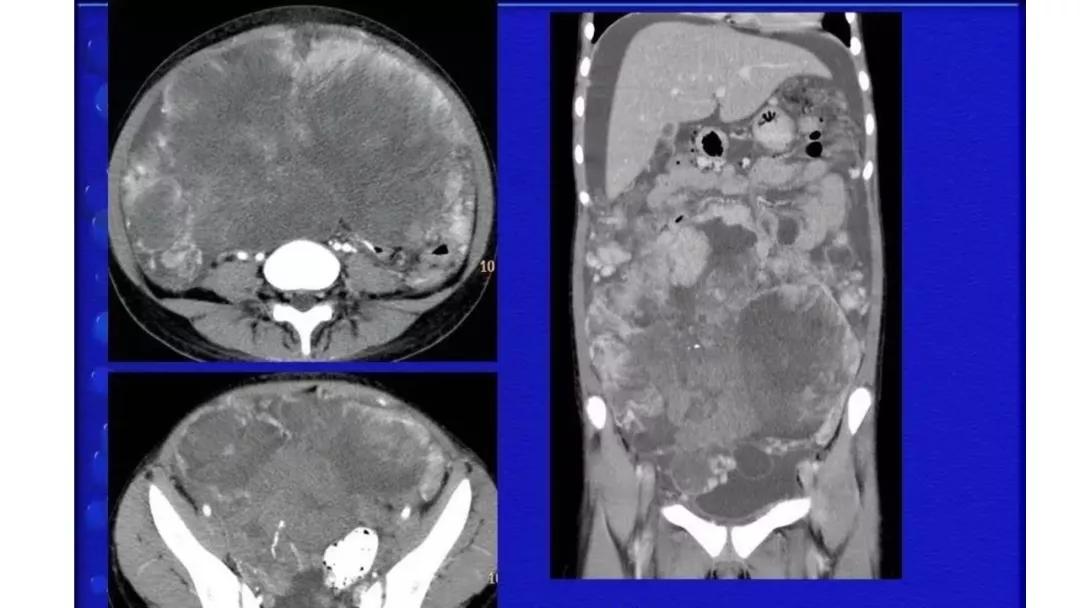

AFP升高:卵黄囊瘤、无性细胞瘤、混合瘤

恶性者常呈实性或混杂性肿块,多数边界清楚,可伴有不规则沙粒状钙化。无性细胞瘤常为实性肿块,轻度强化,内胚窦瘤实性成分明显强化,不成熟畸胎瘤呈混杂密度。结合年龄及临床生化检查,有助于诊断。

生殖细胞肿瘤占卵巢肿瘤的20%,以成熟畸胎瘤-皮样囊肿多见,良性多,恶性少。表现为囊实性混合性或实性肿块,大多数含有脂肪、钙化等特征。